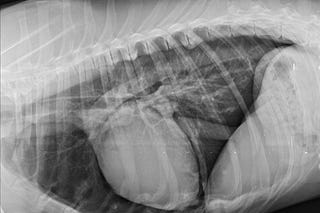

Colocación de un stent traqueal en un perro con colapso traqueal

Abordamos paso a paso la colocación de este dispositivo en un perro con colapso traqueal severo